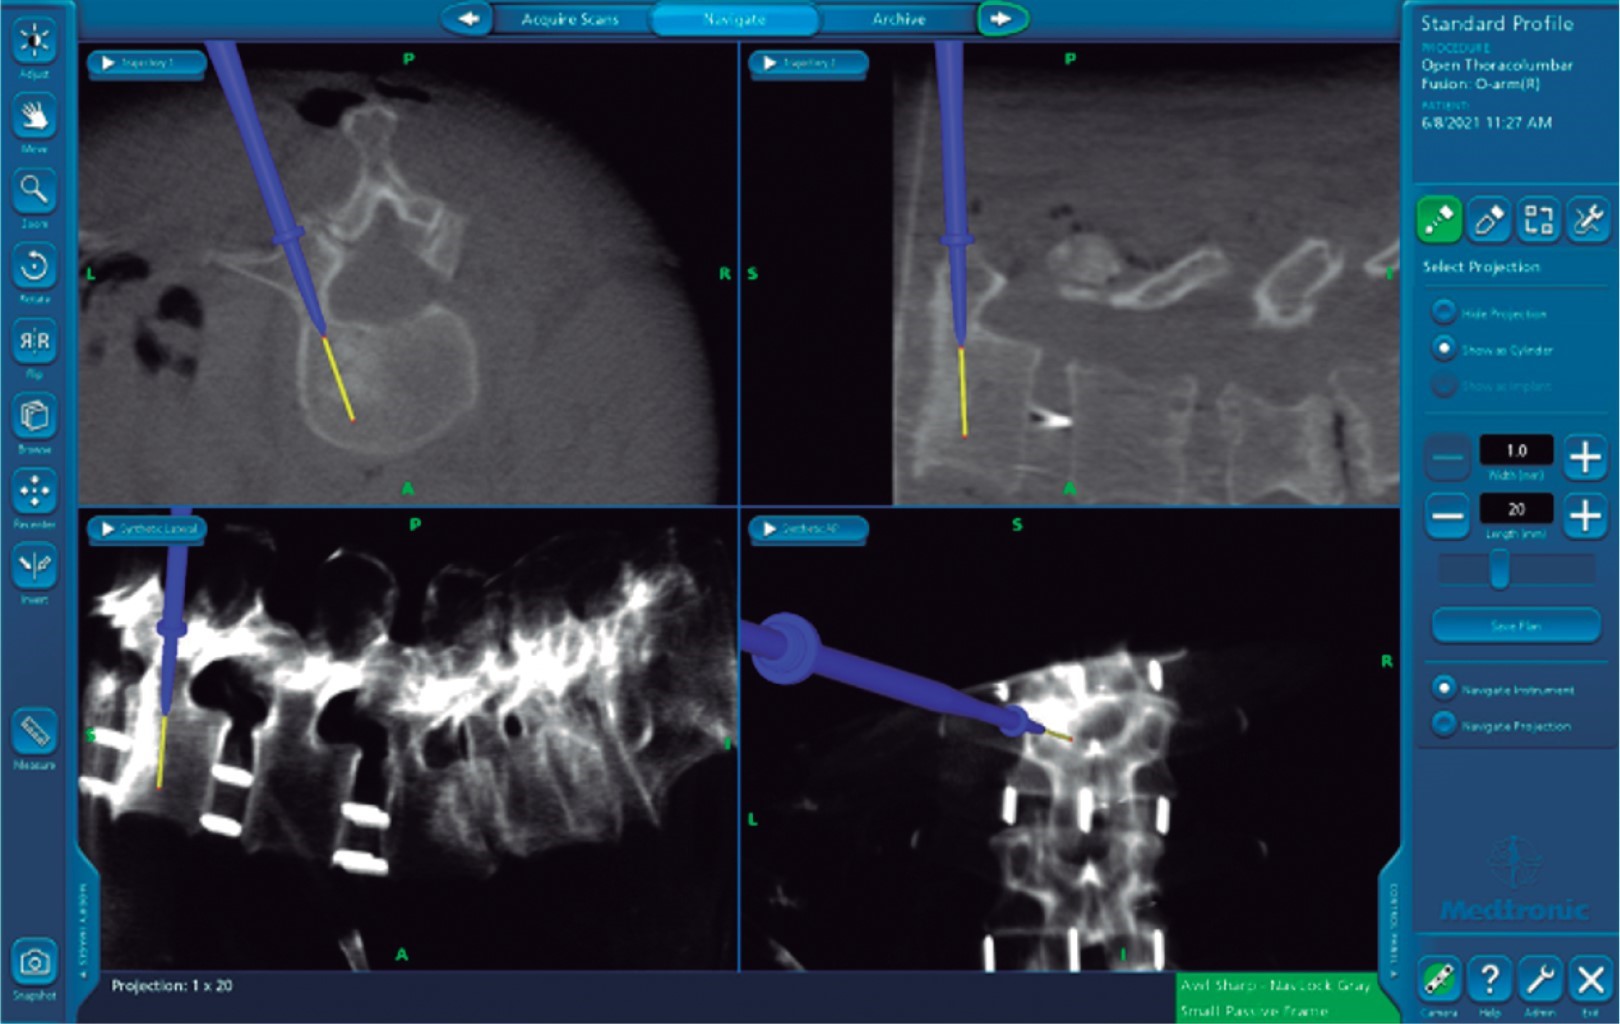

Tratamiento: corrección de escoliosis, mixta XLIF T12 a L4, tornillos pediculares de T9-S1 con navegación O-ARM & StealthStation, (TLIF) de L5-S1 y fusión posterolateral (Figuras 5 y 6).

El uso de O-ARM disminuye prácticamente la exposición a radiación al personal médico y de la sala de quirófano, ya que se realiza un único barrido abarcando cinco segmentos por barrido, lo cual conlleva una radiación de 10 Msv.9 El uso de C-ARM nos da fallas hasta de 20% con rupturas de pedículo mayores a 4 mm en 3.8% de los casos detectados con TAC posterior a evento quirúrgico.10 Un 97.5 a 99% de los tornillos colocados con navegación se ponen correctamente (Figura 7).

La asociación de O-ARM con lesión nerviosa va de 1-3%. Con el uso de C-ARM está estimada la falla de colocación de tornillos en segmentos largos hasta de 41% (G0-G1-G2-G3-G4). Con el O-ARM, el mayor desplazamiento que se espera es un G0-1 < 2 mm.3 Con O-ARM el tiempo estimado de colocación de tornillo es de 2-8 min. A diferencia de C-ARM (15-20 min) en O-ARM (Figuras 8 y 9). Como limitación, existe el costo y la diferencia medida con el punzón del tornillo real 3.14 mm. Se ha reportado que de cada 436 tornillos colocados, sólo existen 4 fallas cuando se unen O-ARM Y NAVEGACION (0.9%), y aun así, demuestra una baja probabilidad de lesión nerviosa al ser colocados como G0-G1 (Figura 10).

Figura 5

Figura 6

Figura 7

Figura 8

Figura 9

Figura 10